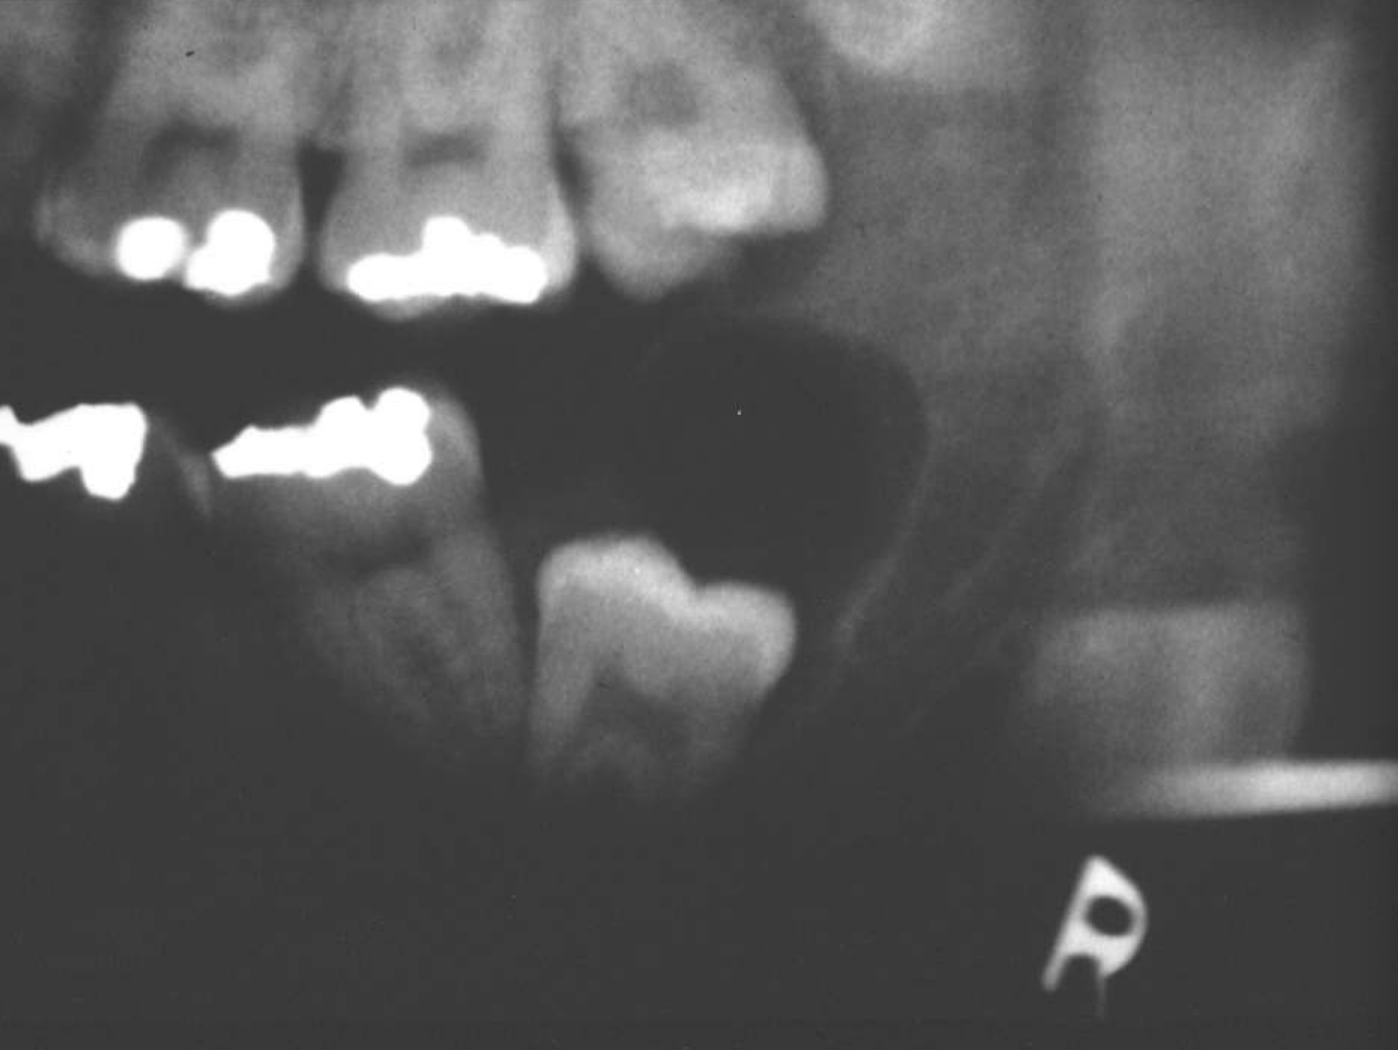

ameloblastoma

Multilocular

Septae appear coarse

Thinning of inferior mandibular border

Displacement of teeth

Displacement of inferior alveolar nerve canal